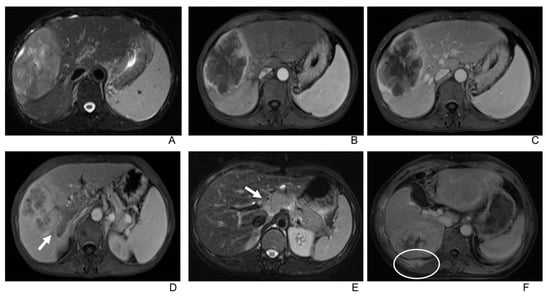

3.2. Imaging Manifestations

- Only two lesions showed a scar-like enhancement in the tumor in AP.

- Two tumors had associated satellite lesions.

- Four patients had portal vein tumor thrombosis (Figure 3).

- Three patients exhibited intrahepatic biliary dilation, and one patient had distal metastasis on the 12th rib (Figure 3).

- Furthermore, lymph node enlargement was found in 9 patients, and metastases were discovered pathologically in 11 patients. The median short-axial diameter of the lymph node was 2.1 cm (range, 0.7 cm to 2.9 cm). Only two lymph nodes had necrosis inside, while the others all showed homogeneous hypervascular enhancement.

- Two patients underwent the gadoxetic acid-enhanced MRI, and both tumors showed hypointense in the hepatobiliary phase.